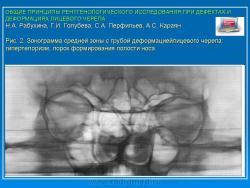

Рис. 2.Зонограмма средней зоны с грубой деформациейлицевого черепа: гипертелоризм, порок формирования полости носа